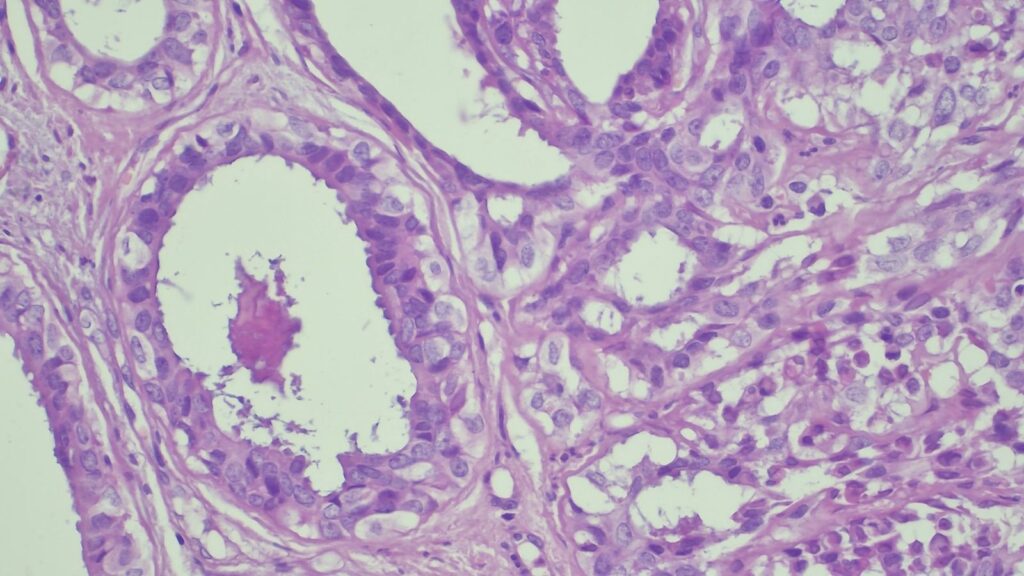

✅ 腺体发育良好,呈圆形和分叶状结构。 ✅ 边缘虽略不规则,但整体呈推挤性(pushing)和局限性生长。 ✅ 无弥漫性浸润结构。 ✅ 无促结缔组织增生性间质反应(No desmoplastic stromal reaction,这是排除浸润癌的核心点)。 ✅ 细胞学形态温和(Bland cytology)。 ✅ 在慢性炎症和纤维化的背景下,仅见单个典型的核分裂象。 在病变外周,腺体表现出被瘢痕样间质压迫和塑形的特征,而不是破坏性或浸润性生长。

🔬 【免疫组化(IHC)进一步证实良性】

CK7: 阳性 (+) CK20: 阴性 (-) p53: 野生型表达模式 Ki-67: 增殖指数极低 🎯 【最终诊断】 综合所有特征,该病变最符合与慢性肛瘘相关的良性/反应性腺体组织,极有可能是被闭塞/嵌顿的肛腺或肛管残余(Entrapped anal gland or duct remnant),而非腺癌!